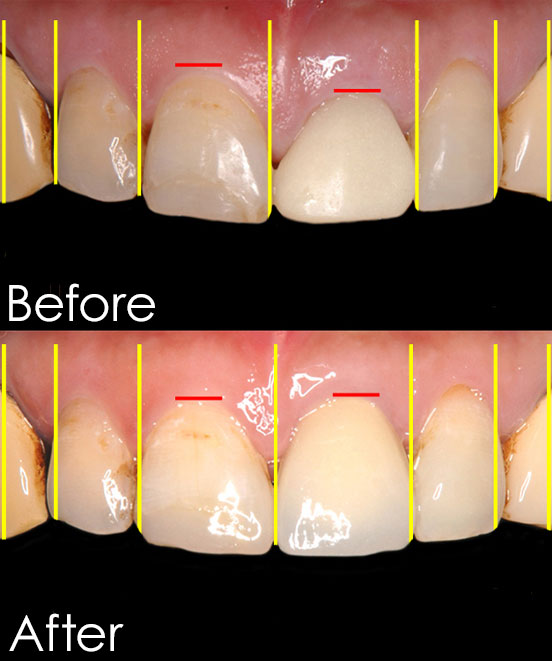

男性Cさん(30代会社員)

お悩み:歯の色が気になる

治療内容:オフィスホワイトニングで歯の白さをとりもどしてから、ご自分の歯の色にあわせてジルコニアセラミックを被せる治療を行いました。

治療期間:ホワイトニング:1ヶ月、ジルコニア:約2週間

治療回数:ホワイトニング:2回、ジルコニア:2回

金額:オフィスホワイトニング 44,000円(税 込)

セラミック治療 134,000円(税込)

リスク・副作用:ホワイトニング後はしみる可能性がある。ジルコニアセラミックを被せるために歯を削る必要がある。